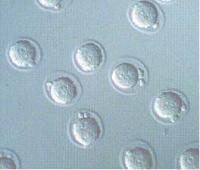

Tökéletesen ellenőrzött babák születtek

Egészséges babáknak adott életet az a két nő, akiknek megtermékenyített petéit teljes genetikai vizsgálatnak vetették alá, mielőtt visszaültették azokat a méhükbe. A kísérletben használt új technológia javíthatná a mesterséges... » 1 hozzászólás

A fagyasztott embriókból egészséges babák születnek

Egy dán kutatás szerint az embrióként lefagyasztott, majd beültetett lombikbabáknak kisebb az esélyük koraszülöttségre és a kis testsúlyra, mint a friss embrióként fogant társaiké. Az orvosok szerint ezek az eredmények azt... »